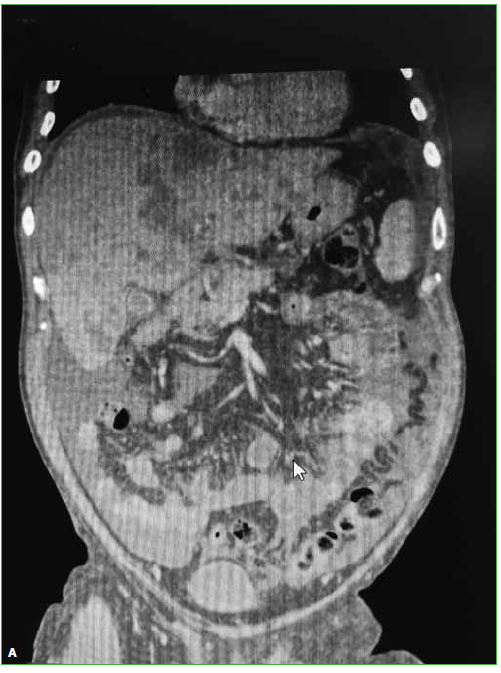

Las hernias discales intraesponjosas vertebrales o nódulos de Schmörl consisten en una herniación o una extrusión del núcleo pulposo del disco intervertebral a través del platillo vertebral hacia el cuerpo adyacente. Suelen asociarse a deformidades vertebrales, como la enfermedad de Scheuermann, o a enfermedades reumáticas, como la espondilitis anquilopoyética. En general, son hallazgos casuales y cuadros asintomáticos; son pocos los casos publicados de nódulos sintomáticos. Su aparición estaría relacionada con un platillo vertebral debilitado por traumatismo o estrés repetido. Cuando el nódulo es agudo o reciente, puede ser difícil diferenciar la degeneración benigna de una infiltración maligna o una infección. Presentamos un caso inusual de un nódulo de Schmörl doloroso en un hombre sin antecedentes de relevancia, que enmascaró una lesión metastásica de carcinoma pancreático a nivel lumbar. Se realiza una revisión bibliográfica. ABSTRACTIntraosseous disc herniation –or Schmörl nodes (SN)– are a herniation or prolapse of the nucleus pulposus of the intervertebral disc through the vertebral plate and into the adjacent vertebral body. They are usually associated with vertebral deformities, suchas Scheuermann’s disease, or rheumatic diseases, such as ankylopoietic spondylitis. In general, they are spontaneous and asymptomatic findings, and there are only a few reported cases of symptomatic nodes. The etiology is supposedly related to a weakened spinal plate due to trauma or repeated stress. When the node is acute or recent, it can be difficult to differentiate a benign degeneration from a malignant infiltration or infection. In this paper, we discuss the unusual case of a painful Schmörl node in a man with no relevant history and a masked metastatic lumbar spinal tumor originated from pancreatic cancer. We performed a literature review.Descargas